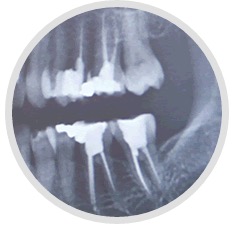

Endodontie

Endodontie - auf deutsch: Wurzelbehandlung - ist nötig, wenn ein Zahn mal stärker erkrankt oder entzündet ist... Ein solcher Zahn ist aber nicht sofort verloren. Durch eine Wurzelbehandlung kann man diese Zähne oft noch Jahre erhalten.